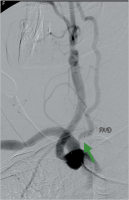

Atherosklerose

Abbildung 3: Atherosklerotisches Art. carotis-interna-Aneurysma links (grüner Pfeil).